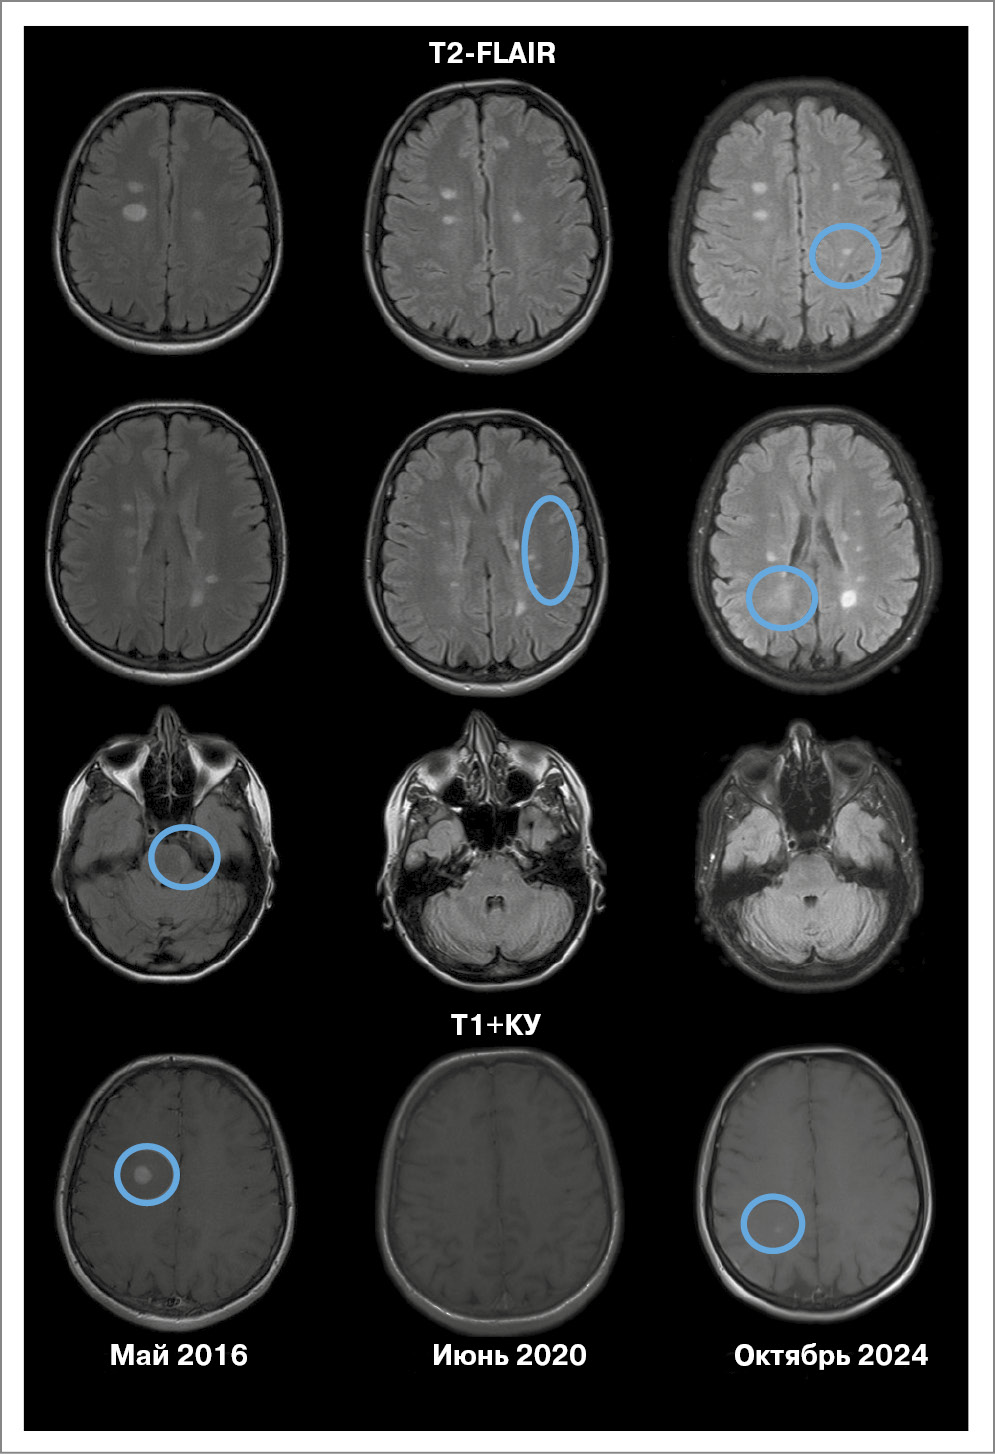

Пациент Д., мужчина, 1986 г.р. Дебют заболевания в 2017 г. (возраст 30 лет), когда появилось двоение в глазах, головокружение, слабость в левой ноге. По данным МРТ головного мозга: множественные очаги в белом веществе головного мозга – перивентрикулярные, в том числе в мозолистом теле, юкстакортикальные в мозжечке (рис. 1) и шейном отделе спинного мозга.

Рис. 1. МРТ пациента Д. (клинический случай 1).

Выполнено исследование сыворотки и ликвора на олигоклональные антитела, тип синтеза 2. Поставлен диагноз «РС, ремиттирующее течение».

Проведена пульс-терапия метилпреднизолоном в курсовой дозе 6 г с положительным эффектом, зарегистрировано снижение балла EDSS до 2,5. Назначен ПИТРС ИНФβ-1b (Инфибета®, АО «Генериум») 9,6 млн МЕ подкожно через день. На фоне 7 лет терапии препаратом Инфибета® клинических обострений не зарегистрировано. Отмечалась активность по данным МРТ в виде появления нового очага перивентрикулярно в течение первых 6 мес от начала терапии и в 2021 г. – появление очага перивентрикулярно, накапливающего контрастное вещество (см. рис. 1). С пациентом обсуждалась возможность замены терапии на другой ПИТРС. Однако он принял решение продолжить лечение ИФНβ-1b. При повторных исследованиях до 2024 г. радиологическая активность отсутствует, EDSS остается стабильным – 2,0 балла.